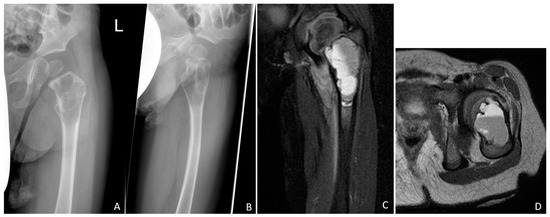

Stabilisation of Pathologic Proximal Femoral Fracture near the Growth Plate with Use of a Locking Plate and Transphyseal Screws

2.1. Case Report